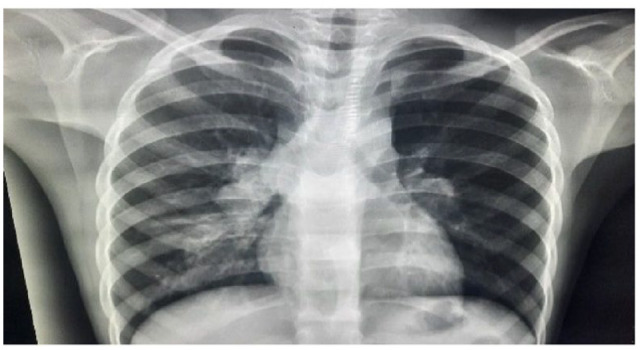

Rosai Dorfman disease (RDD) is a rare non-Langerhans histiocytic disorder, which belongs to the R group of the 2016 revised histiocytic classification. It's characterized by the accumulation of activated histiocytes in the sinusoids of lymph nodes and/or extranodal tissues. Herein, we report a 7-year-old female who was initially suspected to have a lymphoma but was later identified as having RDD. She presented with a history of fever, night sweats, and weight loss, and on physical examination had bilateral cervical lymphadenopathy. Histologic examination of the biopsied cervical lymph nodes showed distended sinuses with S100 and CD68 immunoreactive histiocytes demonstrating emperipolesis, confirming a diagnosis of RDD. The condition is known to be self-limiting. However, evidence from literature and our case management shows that medical therapy can hasten remission in pediatric cases.